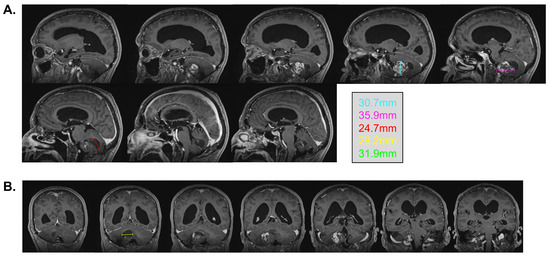

In February 2022, at the age of 72 years old, the patient was hospitalized in his hometown following the appearance of symptoms and was referred to neurosurgery. He mainly displayed loss of balance, unexplained loss of weight, confusion, and psychomotor retardation. He was able to ambulate without the aid of a walker, albeit at a very slow pace. Dexamethasone failed to improve his condition. An MRI underlined a right-sided, cerebellar intra-axial lesion located at the anterolateral portion of the cerebellar hemisphere. The lesion, determined to be a relapse of the initial HBL, displayed a nodular component in intimate proximity with the brainstem, measuring 36.2 × 32.1 × 31.9 mm (Figure 3). The presence of two cystic components were also noted. The first, located posteriorly, measured 32 mm maximally (Figure 4, blue marker). The second, located antero-infero-medially, measured 21 mm maximally and protruded in the subarachnoid space at the level of the pons (Figure 4, pink marker). The lesions caused a mass effect on the medulla, the inferior aspect of the pons, the middle cerebellar peduncle, and at the level of the 4th ventricle with associated hydrocephalus.

Figure 4. Pre-surgical MRI of the lesion. Representative capture of the T2-weighted MRI pre-surgical imaging highlighting the two cystic components of the lesion. Coronal images are organized left to right and represent a posterior-to-anterior progression in the coronal plane. The pink marker highlights a 21 mm antero-infero-medial cystic lesion, while the blue marker highlights a 32 mm posterior cystic lesion.